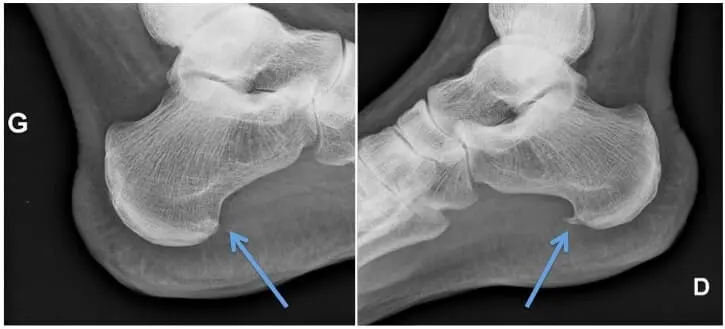

The medical term for ” plantar fasciitis refers to an inflammation of the insertion of the plantar fascia on the heel bone (calcaneus). The plantar fascia is a broad band of fascial relatively rigid, which extends from the region heel piece to the toes. It is in fact a kind of extension of the Achilles tendon. This structure is not very elastic and plays an important role in the stabilization of the arch of the foot during movements of walking and standing.